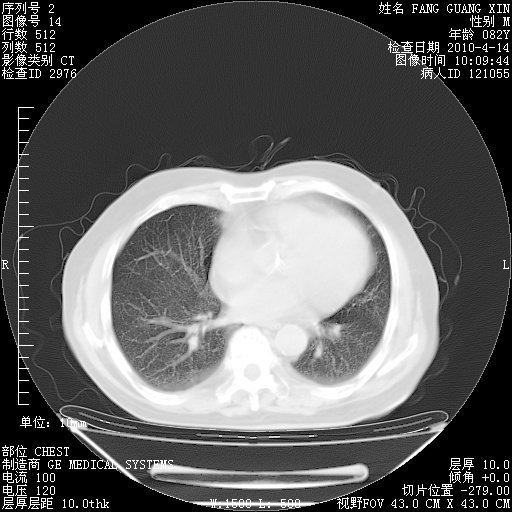

肺部CT平扫未见异常。